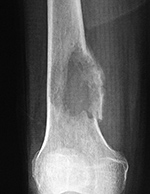

Allografts (tissue grafts between donor and recipient of the same species but of disparate genotypes) are also commonly used (figure: cadaver limb sparing allograft; figure: tibia allografts). These represent treated cadaver bone from the donor bone bank. The disadvantages associated with allografts include possible disease transmission, immunogenicity concerns, poor biologic and mechanical properties, increased cost, and unavailability worldwide due to financial and cultural issues (Ruedi, 2007; Hunter, 2003; Parikh, 2002).

AP and lateral views of the knee show a distal femoral cadevaric limb sparing allograft approximated to the native distal femoral stump by a retrograde intramedullary nail. Two interlocking cannulated screws go through the distal portion of the nail. Cruciate ligament and capsular reattachment were performed with two interference screws and two staples in the proximal tibia and a staple in the posterior aspect of the allograft metaphysis. The patient had a non-specified distal femur sarcoma.